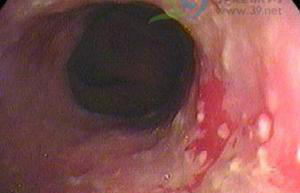

小编导读:食管炎食管中段黏膜破损,片状发红。……食管炎食管中段黏膜破损,片状发红。